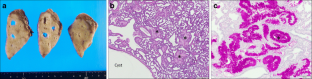

Fig. 4